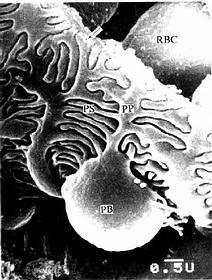

兔肾小体扫描电镜像

图15-7 兔肾小体扫描电镜像 示足细胞

PB足细胞体,PP初级突起,PS次级突起,RBC红细胞

↑基膜(河北医学院电镜供图)

(2)肾小囊(renal capsule)又称Bowman囊,是肾小管起始部膨大凹陷而成的双层囊,似杯状,囊内有血管球(图15-3,15-4)。肾小囊外层(或称肾小囊壁层)为单层扁平上皮,在肾小体的尿极处与近端小管上皮相连续,在血管极处反折为肾小囊内层(或称肾小囊脏层),两层上皮之间的狭窄腔隙称肾小囊腔,与近曲小管腔相通。内层细有胞形态特殊,有许多大小不等的突起,称为足细胞(podocyte)(图15-5,15-6)。足细胞体积较大,胞体凸向肾小囊腔,核染色较浅,胞质内有丰富的细胞器,在扫描电镜下,可见从胞体伸出几个大的初级突起,继而再分成许多指状的次级突起,相邻的次级突起相互穿插成指状相嵌,形成栅栏状,紧贴在毛细血管基膜外面(图15-7)。突起之间有直径约25nm的裂隙,称裂孔(slit pore),孔上覆盖一层厚4-6nm的裂孔膜(slit membrane)(图15-5)。突起内含较多微丝,微丝收缩可使突起活动而改变裂孔的宽度。足细胞表面也覆有一层富含唾液酸的糖蛋白。